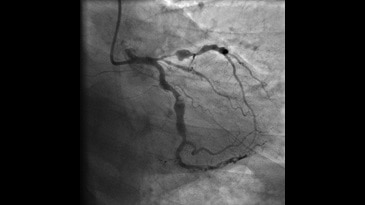

- InnovaSpin — оптимальная проекция сосуда за одну инъекцию контраста. Клиническое приложение для ротационной ангиографии Innova Spin позволяет увидеть всю камеру сердца и анатомию коронарных сосудов за одну съемку и с одной инъекцией контраста;